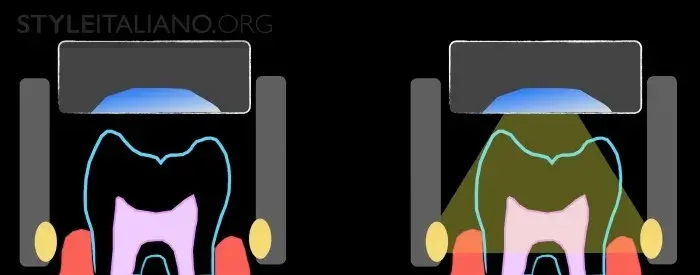

Рис. 3 Устройство Diagnocam, в основе которого лазерно-индуцированное просвечивание, позволяет нам просветить жевательные поверхности зубов. Выражается в серой шкале. Различные ткани зуба реагируют на свет по-разному: эмаль светлая, дентин более серый, а полости гораздо темнее.

DiFOTI (Digital Fiber Optic Trans Illumination) – здесь используется инфракрасное свечение.

Рис. 5 — Лазерный свет, идущий от альвеолярной кости проходит через зуб, а специальная камера фиксирует изображения. Эти файлы затем можно показать пациенту.